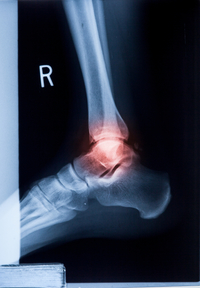

A Sprain A Twist Or A Roll Decipher Your Ankle Injury

Sprained Ankle Recovery Time Orthopedic Associates

How Long Does It Take For A Sprained Ankle To Heal Ny Orthopedics